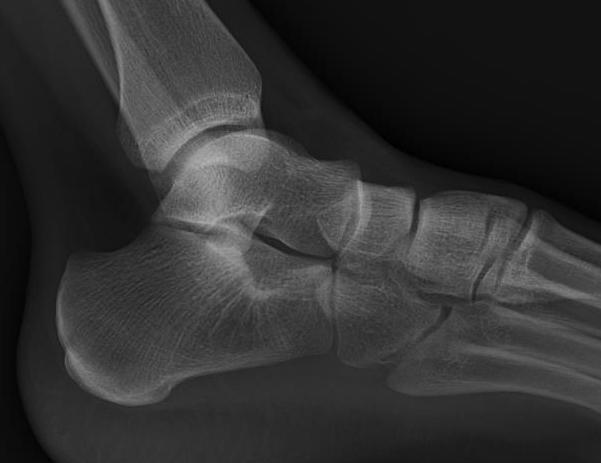

Chopart joints

- talonavicular joint

- calcaneocuboid joint